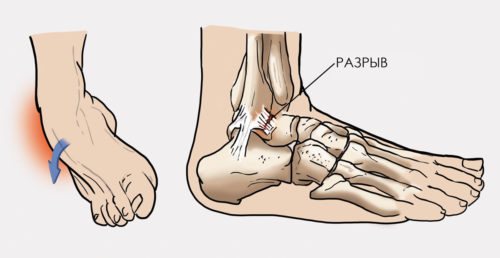

На голеностопе расположено несколько групп связок, представленных на рисунке ниже:

Каждая из них может быть повреждена при неаккуратном движении или чрезмерной физической нагрузке. И даже если возник лишь поверхностный разрыв нескольких волокон, подвижность голеностопа нарушается и все остальные связки перестают полноценно работать. К счастью, мышечно-связочный аппарат владеет свойством регенерации, и все разорванные волокна со временем восстанавливаются.

Виды связок

В районе голеностопного сустава расположено 3 разновидности связок:

- Наружные, которые закреплены во внешней стороне лодыжки.

- Внутренние, которые крепятся к внутренней щиколотке.

- Межкостные, которые соединяют большую и малую берцовые кости.

Фиксация сустава осуществляется 3 группами связок — внешними, внутренними и межберцовыми. Чаще других у потерпевших отмечаются разрывы в переднем таранно-малоберцовом наружном соединительнотканном тяже.